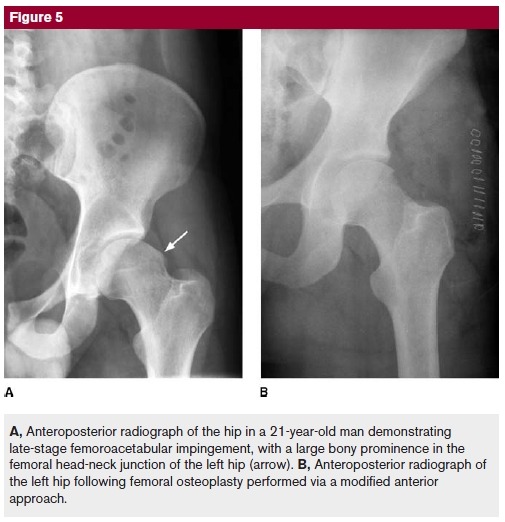

Evidence is emerging that subtle morphologic abnormalities around the hip, resulting in femoroacetabular impingement, may be a contributing factor in some instances to osteoarthritis in the young patient. The morphologic abnormalities result in abnormal contact between the femoral neck/head and the acetabular margincausing tearing of the labrum and avulsion of the underlying cartilage region, continued deterioration, and eventual onset of arthritis.

Nonsurgical treatment typically fails to control symptoms. Surgical management involves dislocation of the hip(while preserving the blood supply to the femoral head) and femoroacetabular osteoplasty. Encouraging results have been

reported following femoroacetabular osteoplasty and arthroscopic treatment of femoroacetabular impingement.

- Pincer impingement(acetabulat cause of FAI/ 대퇴골두의 범위를 넘어갈 때 )/ CAM impingement(femoral cause of FAI/ femoral head-neck junction의 aspherical portion에 기인)